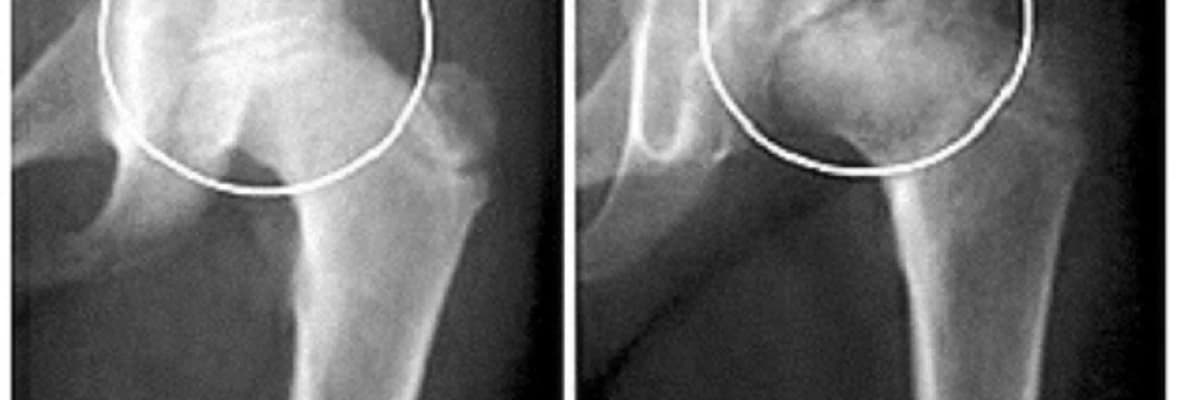

Xəstəlik halında fiziki müayinə ilə birlikdə rentgen filmi çəkilir. Ümumiyyətlə, rentgen müayinəsi ilə xəstəliyi müəyyən etmək mümkündür. Çox erkən mərhələlərdə problem rentgendə görünməyə bilər. Bu zaman uşağın ağrıları keçmirsə, təkrar müayinə üçün rentgen çəkilməlidir. Uşaq ortopedi tərəfindən MRT və ya sintiqrafiyanın tövsiyə edildiyi hallar olsa da, adətən yalnız rentgen filmi kifayətdir.

Perthes 4 mərhələdə görünür. Xəstələr adətən ikinci mərhələdə ilk simptomları yaşayır və həkimə müraciət edirlər. Üçüncü mərhələdən dördüncü mərhələyə keçdiyimiz zaman sümük ölümü bud sümüyünün sümüyünün bir hissəsində və ya hamısında baş verir. Bədən ölü toxumaları əvəz etmək üçün yeni sümük yaradır. Yenidənqurma mərhələsində müalicənin məqsədi; bud sümüyü başını bud oynağının yuva hissəsinin içərisində saxlamaqdır. Bu məqsədlə zərurət yarandıqda bəzi cərrahi əməliyyatlar uşaq ortopedləri tərəfindən aparılır. Bəzi hallarda gec diaqnoz qoyulan və irəliləmiş mərhələdə müşahidə olunaraq, müşahidə və fizioterapiya protokolu ilə müalicəyə üstünlük verilə bilər və uşaq böyüdükcə cərrahi müalicələr hazırlanır.